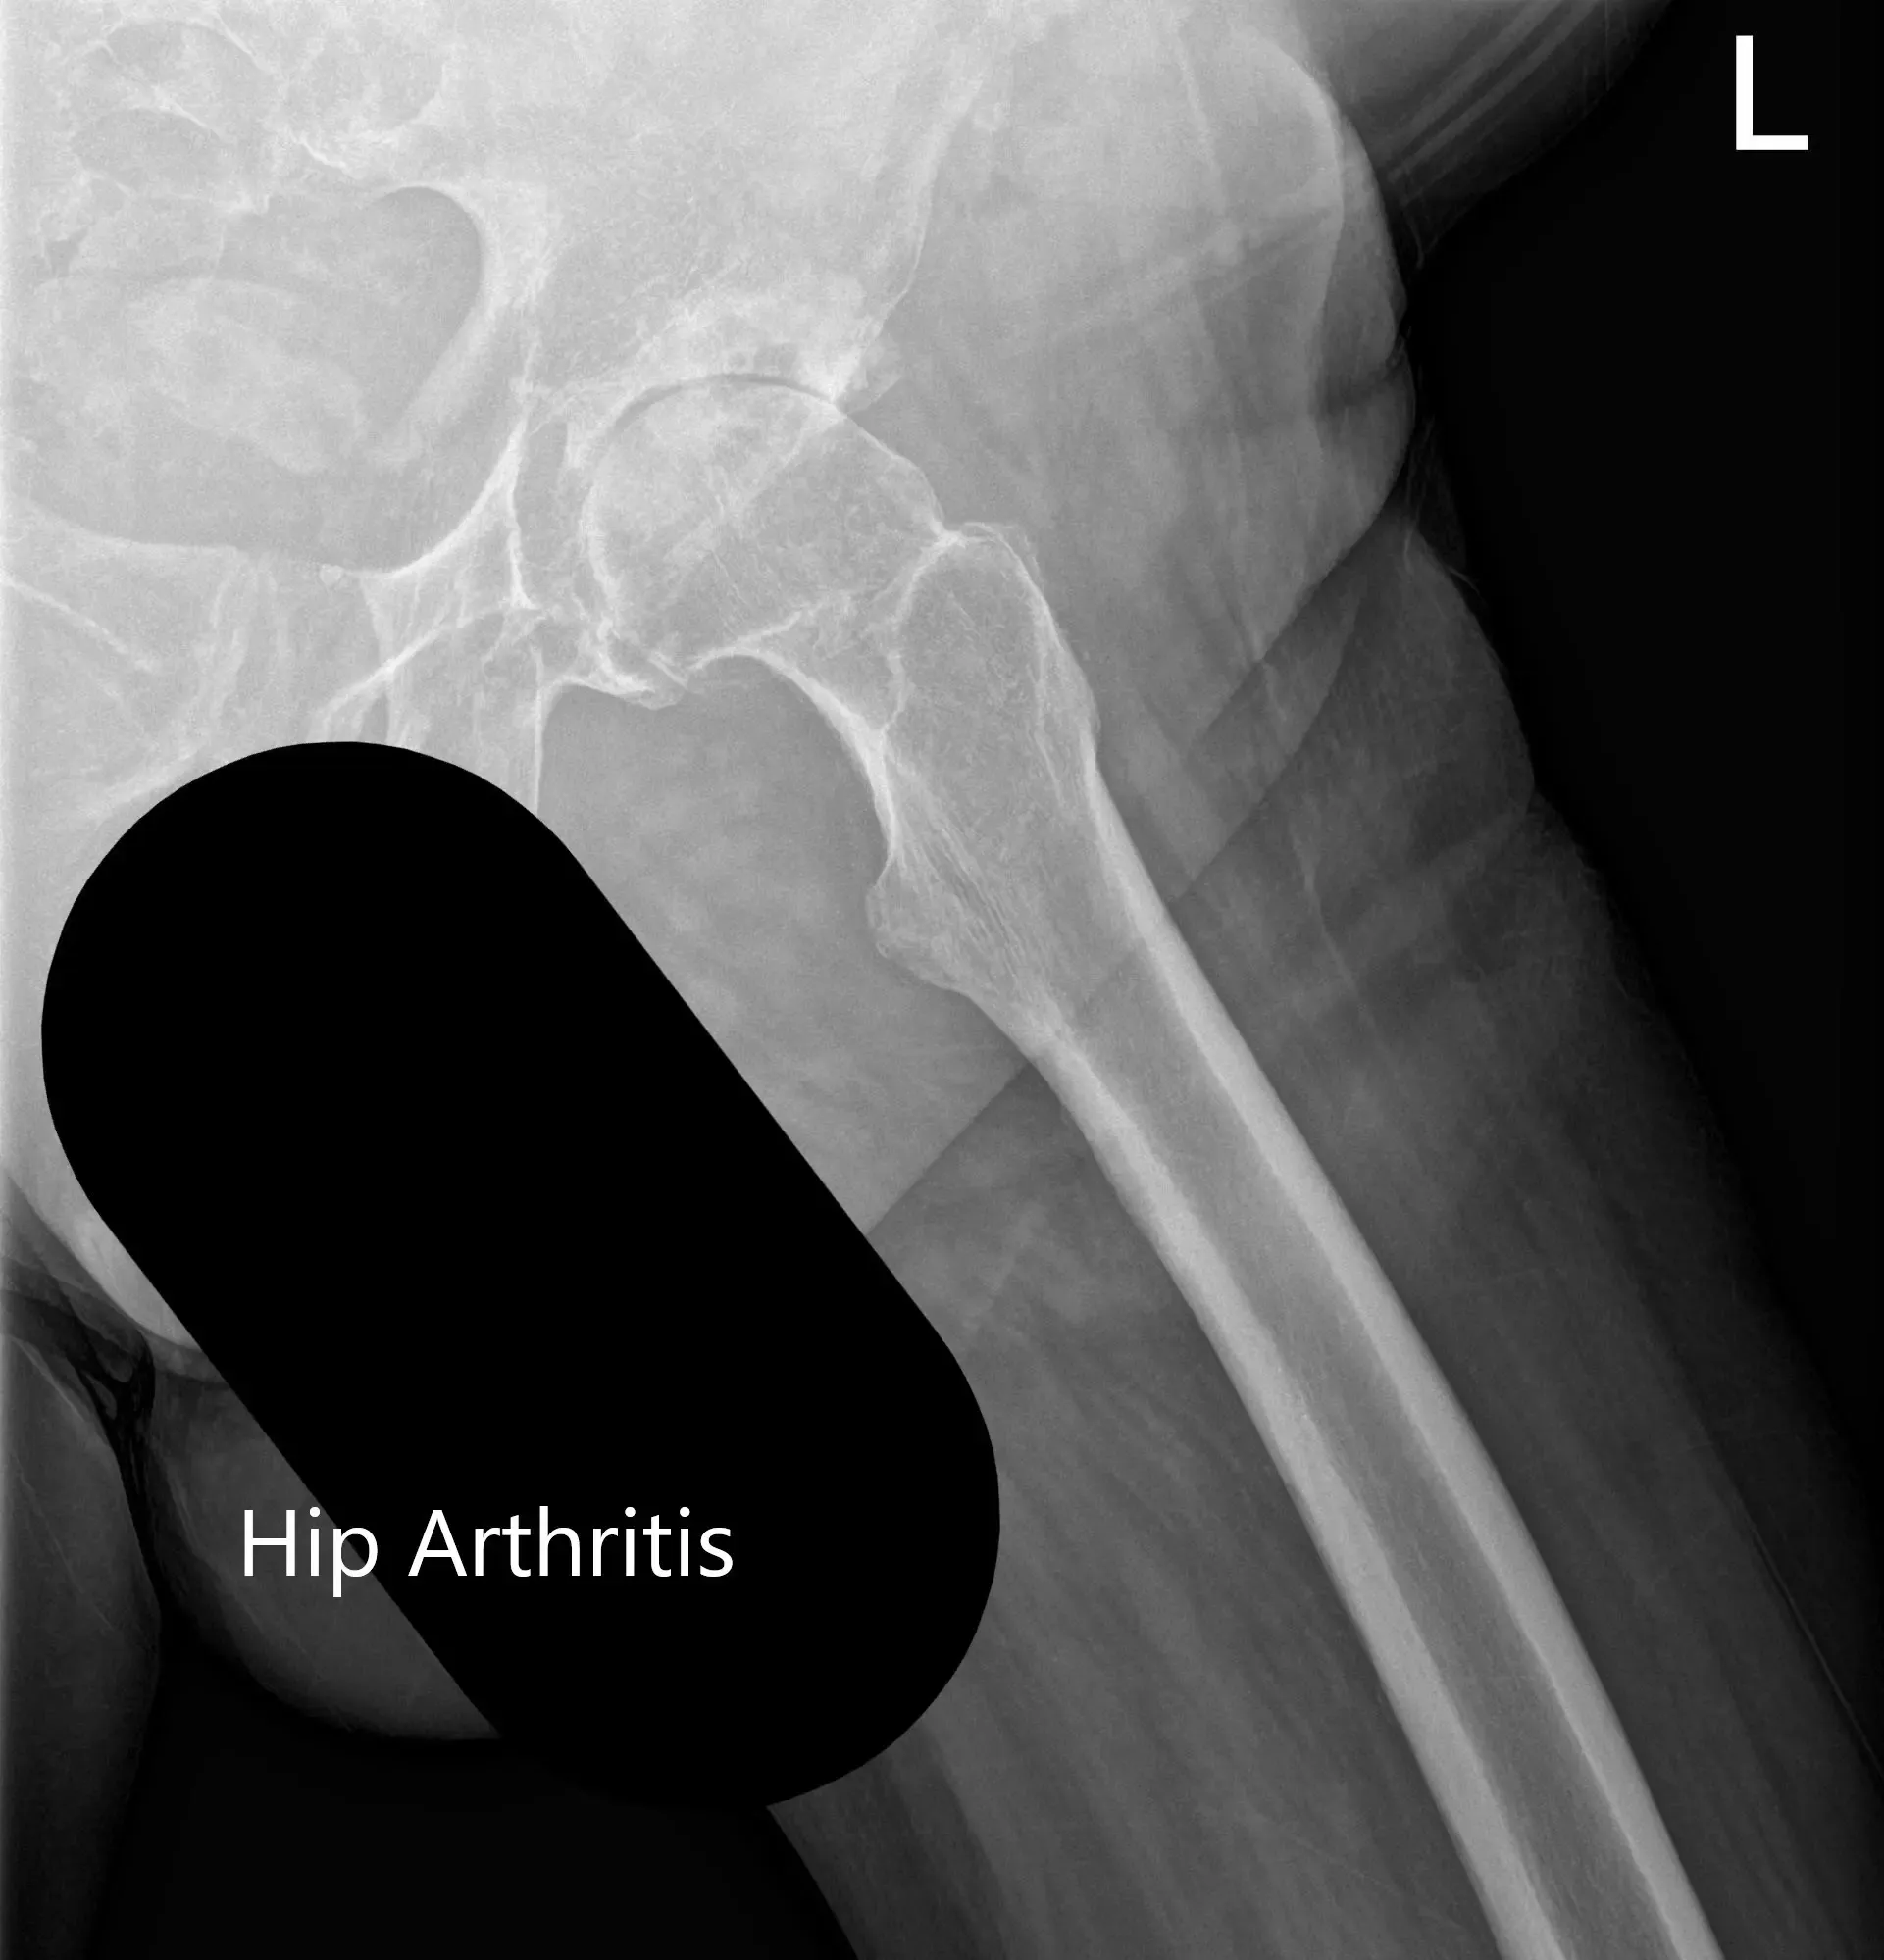

Las imágenes revelaron cambios osteoartríticos en la articulación izquierda de la cadera con reducción del espacio articular, quiste subcondral, esclerosis y osteófito. Tras agotar las opciones de manejo conservador, se recomendó al paciente una prótesis total de cadera. Se discutieron extensamente con el paciente los riesgos, beneficios y alternativas. Ella aceptó seguir adelante con el procedimiento.

Radiografía preoperatoria que muestra la vista Judet de la pelvis.

Radiografía preoperatoria que muestra la vista lateral en forma de rana y la vista en ángulo de la cadera izquierda.